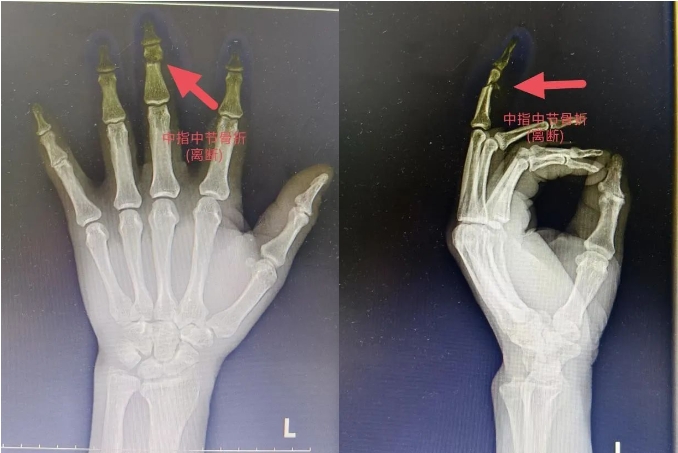

术前手正斜位X片

急诊行显微镜下断指再植手术治疗。